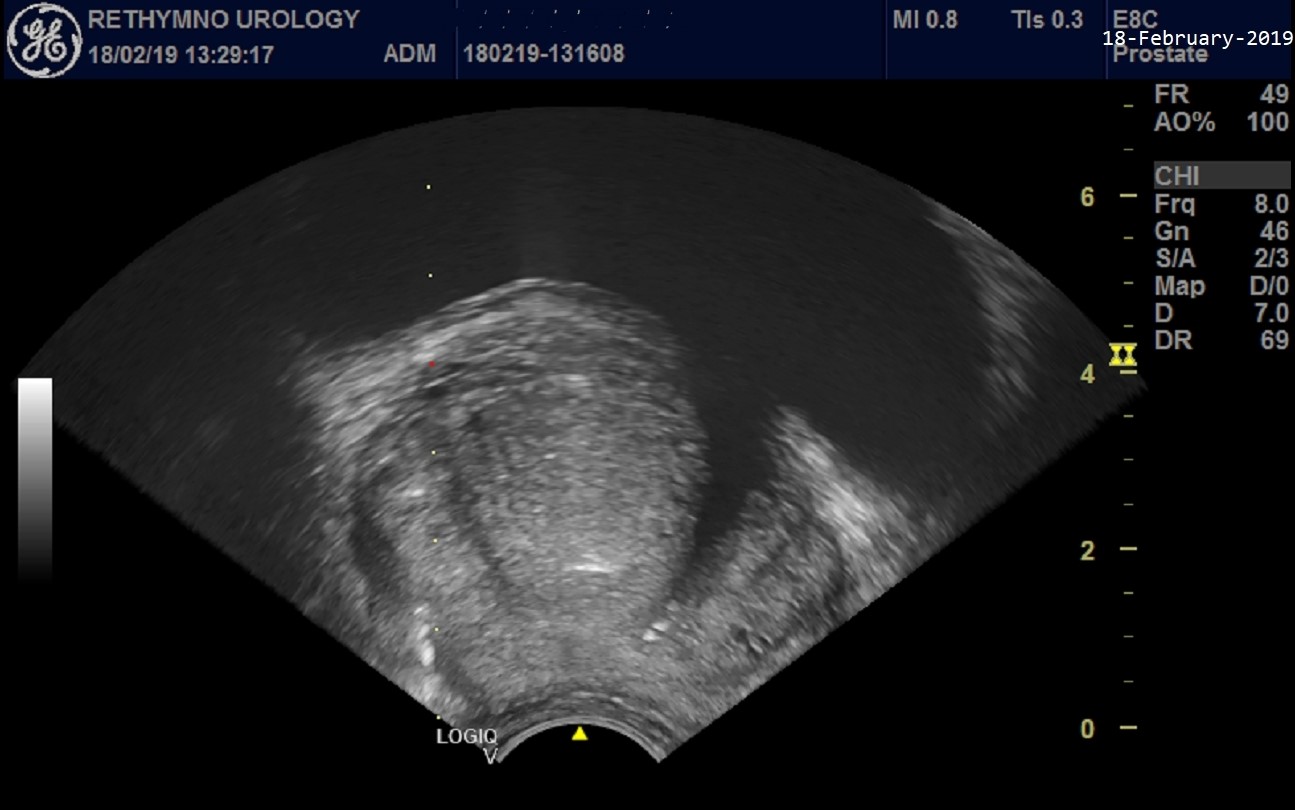

Ο διορθικός υπερηχογράφος είναι μία λεπτή κεφαλή υπερήχου που με τοπική αναισθησία (αναισθητικό τζελ) εισέρχεται στο ορθό από τον πρωκτό μετά από αντισηψία της περιοχής. Χρησιμοποιεί υψηλής συχνότητας κύματα και παράγει λεπτομερείς εικόνες του προστάτη. Αυτό βοηθά πολύ στην μέτρηση του όγκου του προστάτη και την εύρεση ύποπτων περιοχών. Στη συνέχεια με μία ειδική βελόνη μπορεί να γίνει αναισθησία γύρω από τον προστάτη, συμπληρωματικά. Ακολουθεί με ένα ειδικό εργαλείο (αυτόματο μπιστόλι βιοψίας) η λήψη των ιστο-τεμαχιδίων που είναι συνήθως 12 έως 18, ανάλογα με τον όγκο του προστάτη. Ίσως νοιώσετε μία μικρή ενόχληση αλλά σπάνια υπάρχει ενοχλητικός πόνος. Η όλη διαδικασία κρατά 15-20 λεπτά. Ο ιατρός μπορεί να σας κάνει μία συμπληρωματική ενέσιμη αντιβίωση πριν ή αμέσως μετά τη βιοψία.